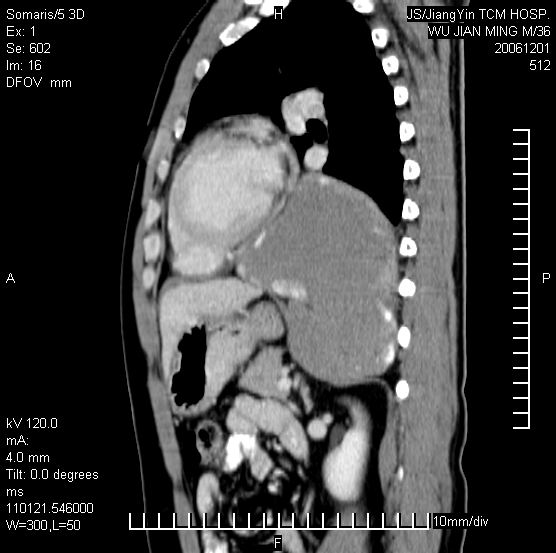

以下是引用dyqct在2006-12-1 21:17:00的发言:[br]左心缘旁及后肋膈窦区见巨大椭圆形混杂密度肿块,周围见大小不等斑片状钙化,内部无强化,周围包膜轻度强化,心脏明显受压变形,即明显占位效应,肿块广基与心包、膈相连。肝、脾内、肝门见多数小结节状钙化影。[br]考虑:1、左心缘旁及后肋膈窦区慢性包裹性胸膜炎(结核性);[br] 2、肝、脾及肝门淋巴结核已钙化。[br]

以下是引用zrs在2006-12-2 17:28:00的发言:[br]肺内、肝脾内虽有钙化,但不支持结核性胸胸膜炎包裹,而支持寄生虫感染![br][br]

以下是引用zyx168在2006-12-2 10:10:00的发言:[br][br]肝脾肺内多发钙化灶